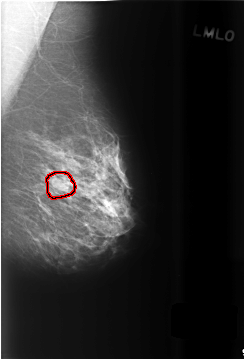

C_0504_1.LEFT_MLO

LEFT_MLO LINES 5744 PIXELS_PER_LINE 3896 BITS_PER_PIXEL 12 RESOLUTION 50 OVERLAY

FILE: C_0504_1.LEFT_MLO.OVERLAY

TOTAL_ABNORMALITIES 1

ABNORMALITY 1

LESION_TYPE MASS SHAPE OVAL MARGINS CIRCUMSCRIBED

ASSESSMENT 3

SUBTLETY 4

PATHOLOGY BENIGN

TOTAL_OUTLINES 1

BOUNDARY